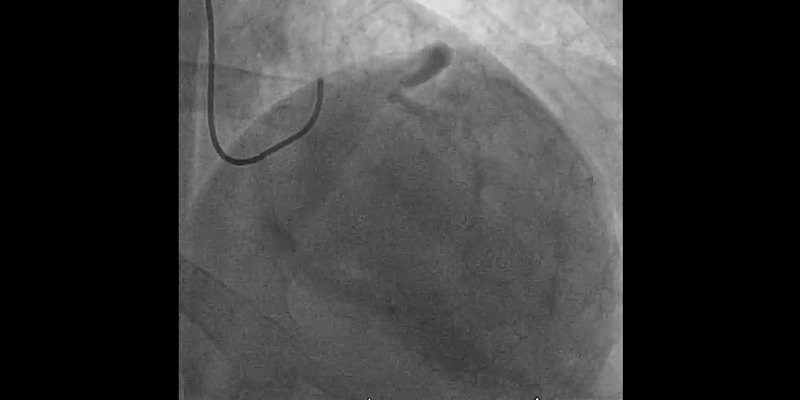

• Step 1: Routine PCI of proximal and distal RCA.

• Step 2: Vessel preparation (Rotational atherectomy + Cutting BalloonTM) of mid LAD to facilitate subsequent balloon dilatation and SynergyTM stent implantation.

• Femoral access: 7 Fr. EBU4 7F Guiding catheter.